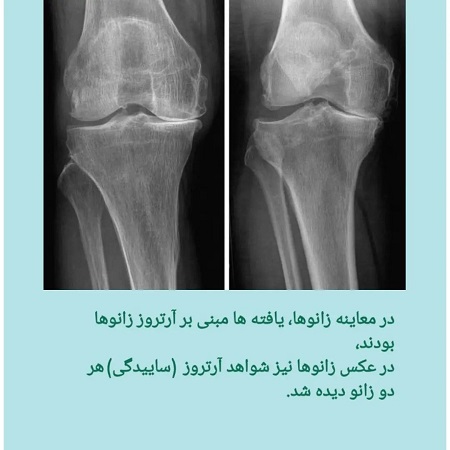

درد زانو با معرفی یک بیمار سپتامبر 1, 2022 کلینیک24 دیدگاه های نوشته خاموش است فهرست مطالب Toggle بررسی درد زانو با معرفی یک بیماراین مطلب برگرفته شده از صفحه اینستاگرام مرکز تخصصی مغز و اعصاب نورون اصفهانمطالب پیشنهادی : بررسی درد زانو با معرفی یک بیمار خانم دکتر فاطمه عباسی متخصص طب فیزیکی و توانبخشی این مطلب برگرفته شده از صفحه اینستاگرام مرکز تخصصی مغز و اعصاب نورون اصفهان مطالب پیشنهادی : اختلال اضطراب اجتماعی لاغری با انجام کارهای خانه رابطه مصرف مکمل ها و میگرن پیشنهاد مطالعهعصبشناسی اجتماعی بهترین توانبخشی اصفهانبهترین فوق تخصص های مغز و اعصاب اصفهانبهترین فیزیوتراپی اصفهانبهترین کاردرمانی اصفهانبهترین کلینیک مغز و اعصاب اصفهانبهترین متخصص مغز اعصاب اصفهانبهترین متخصص مغز و اعصاب اصفهانکلینیک تخصصی مغز و اعصابکلینیک مغز و اعصاب اصفهانمتخصص مغز و اعصابمرکز تخصصی و فوق تخصصی مغز، اعصاب و روان نورون اشتراک گذاری